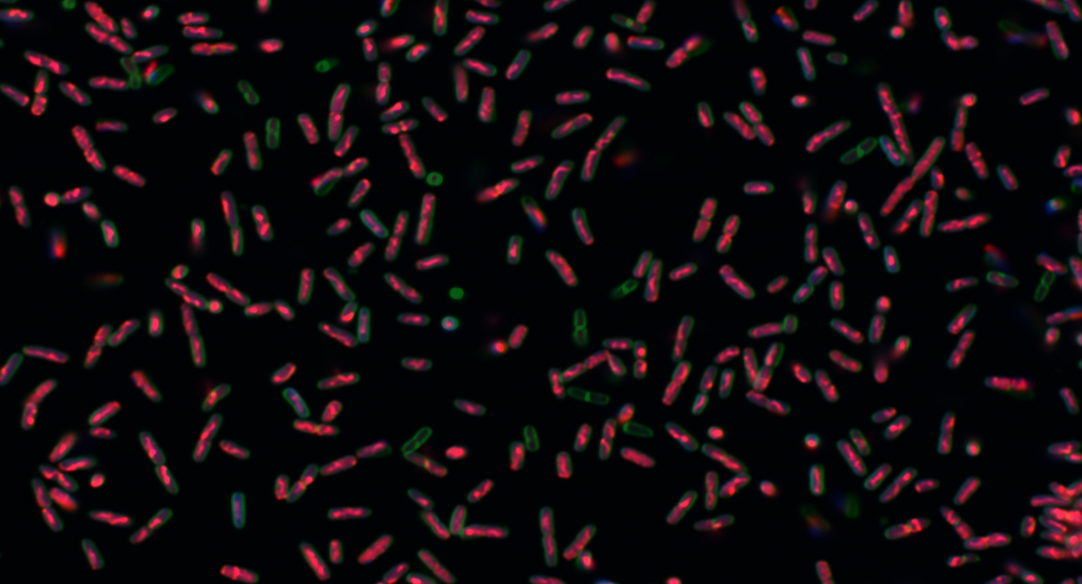

- Two classes of antibiotics against common bacterial pathogens, each with a distinctly novel mechanism of action

- Multiple compound families active against NTM